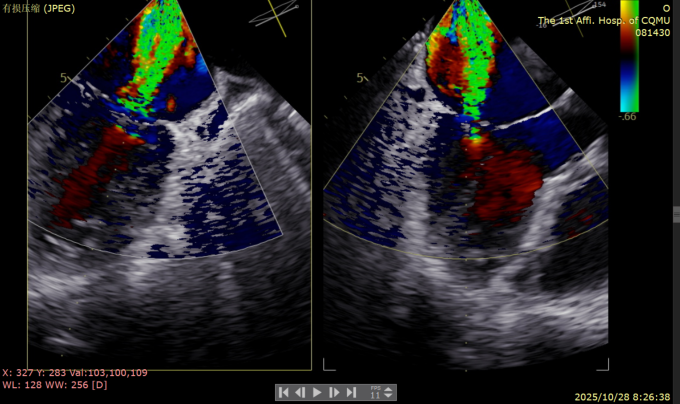

二尖瓣术前评估

复查TTE及TEE检查进一步评估二尖瓣情况。明确为FMR( Carpentier Ⅲb型),二尖瓣后叶栓系,2区瓣叶运动(视频2),重度FMR(4+), 肺静脉逆向血流;2区后叶长度1.15cm,2区前叶长度2.46cm,AP径3.2cm,瓣口面积5.1cm²,房间隔高度3.95cm,瓣叶无钙化,二尖瓣瓣膜条件适合行TEER手术。

图1、图2:2区瓣叶长度(前叶长度2.46cm,后叶长度1.15cm)及彩色血流

患者全麻下行TEER手术。向睿副主任团队穿刺患者右侧股静脉,在X线及食道超声指导下完成房间隔穿刺(视频4)成功获得3.95cm穿刺高度(图4)。再将加硬导丝送至左上肺静脉,20F股静脉扩张鞘充分扩张股静脉穿刺部位,沿加硬导丝将可操纵导引导管(SGC)送入左房。延SGC送入XTR夹子完成骑跨,使用M旋钮使夹子指向二尖瓣(图5)(视频5)。调整Mitraclip输送系统顺利到达二尖瓣目标位置,TEE指导下左房内完成弹道测试和Orientation调整(视频6)。缓慢将XTR夹子送入左室,并三维再次确认夹子轴向和反流位置,缓慢上提夹子使夹臂成功捕获瓣叶(视频7),Gripper Down夹持前后瓣叶并缓慢关闭夹臂(视频9),夹持后反流降至微量(视频10),二尖瓣平均跨瓣压差2mmHg(图6)。评估后将夹子释放。释放后反流微量夹子稳定。术后复查超声证实夹合组织充分,显示微量残余分流。术后二尖瓣平均跨瓣压差2mmHg,肺静脉多普勒波形恢复正常。手术时间持续约1.5小时。

术后复查经胸心脏超声,示肺静脉、肝静脉逆流消失,二尖瓣及三尖瓣反流降低至轻度,手术效果良好。